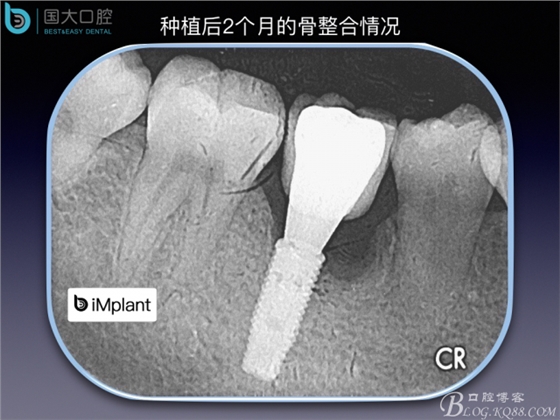

TypeC Socket即刻種植臨床案例